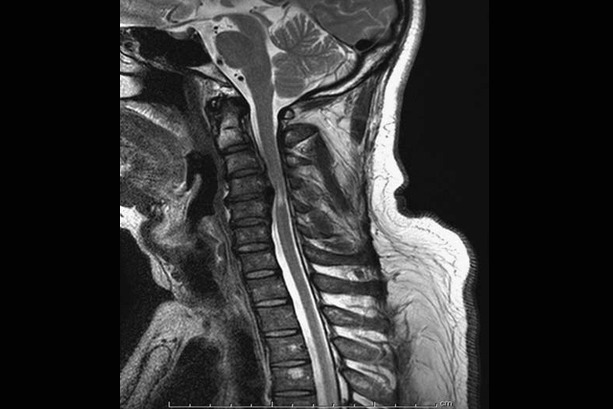

SRF TAKES PRIDE IN PRESENTING TO YOU A FEW INTERESTING CASES

More than 300 Underprivileged Patients have been Operated through our Foundation over the last 15 years !

Cases